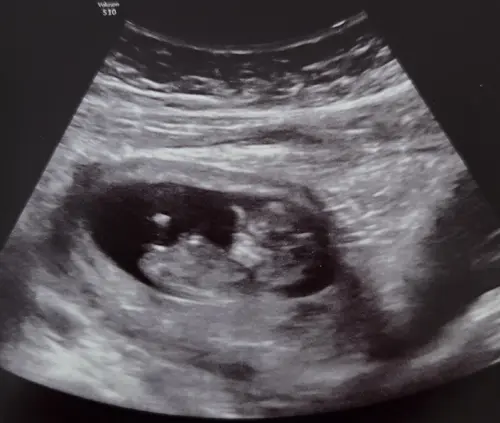

Aahw , ja dit is de mijne maar zn nekploi is te hoog, die van jullie zien er idd annders uit🥺

10w5d hier. Wij hebben a.s maandag de 13 weken echo. Al mijn echo's zullen nu medisch zijn vanwege mono/di tweeling dus vanaf 16 weken zal ik elke twee weken een echo krijgen.

Ik mag geen nipt test meer doen omdat 3.7 van de eerste echo, te hoog is voor een nipt😬

11+6, niks gehoord over de nekplooi :) volgende week 13 weken-echo maar daarbij mogen geen foto’s gemaakt